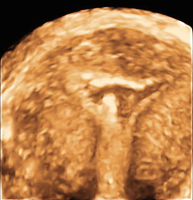

Ultraschall-Serometra

Abbildung 3: Selber Fall wie Abbildung 2 mit 3D-Ultraschall: Zwischen einem dünnen, echodensen Randsaum aus Endometrium hat sich eine Ansammlung von Flüssigkeit mit länglichen, echodensen Strukturen gebildet. Der Stimulationszyklus wurde abgebrochen.

Keywords: 3D-UltraschallCavum uteriGynäkologieIVF-StimulationSerometraSonographie